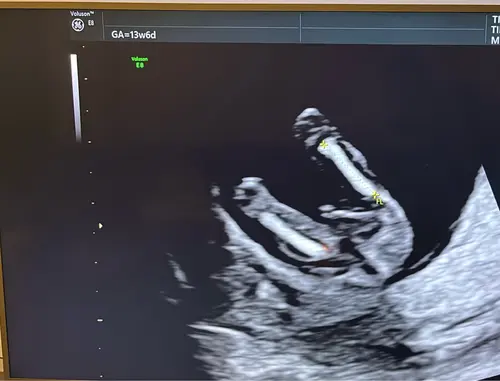

Ik vind het zo knap dat mensen hier wijs uit komen, ik kom er zelf maar niet uit, maar ben stiekem ook wel benieuwd of onze 2de een jongen of meisje is, kan iemand helpen? 😊

Alvast bedankt !

Wellicht dat ik hier tussen kom haha.. ziet iemand wat het is?😂

Duidelijk meisje!